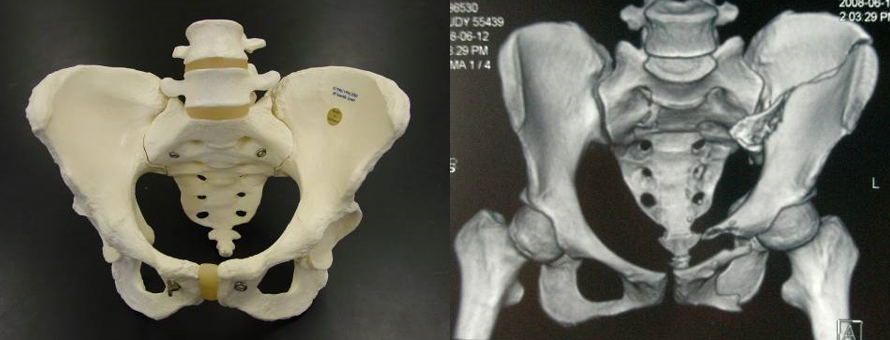

骨盆骨折

骶尾部的椎骨与左、右髋骨连结成骨盆,骨盆保护盆腔内的重要器官(泌尿生殖系)和神经血管。骨盆骨折的并发症主要是血管、膀胱尿道损伤,引起休克或急腹症。

• 绝对卧床休息,取平卧位,避免大幅度翻身,适当协助健侧30°~ 60°卧位。

• 指导正确床上排便方法,避免因抬臀而致骨折再移位。

• 予骨盆固定带固定时,要保持固定带松紧适宜。

骨盆固定带

一、骨盆骨折分稳定性骨折、不稳定性骨折。稳定性骨折者,卧硬板床, 2-4h翻身一次,病人可平卧与健侧卧位交替,翻身时保持骨盆的稳定。严禁坐位及患侧卧位。

二、稳定性骨盆骨折病人翻身方法:1、床上铺一张中单,从床头铺到床尾。2、二或四人翻身法:床的两边站一至二人。(根据病人胖瘦)3、床的两边每人抓住中单的两端,站在床边靠近床头的一人喊口令,共同协作,把病人先移向床的一边。4、靠病人身边的护士抓住中单顺势把病人托起轻轻翻动,另一边的护士抓住中单固定合适位置(一般小于60度),靠病人身边的护士用三角枕支撑背部,协助病人两腿间放枕头。

三、多发骨折或不稳定性骨折者:仰卧硬板床,可予骨盆固定带固定,尽量减少搬动及翻身次数,必须搬动时应多人平托。最好在上外固定架后以后翻身。